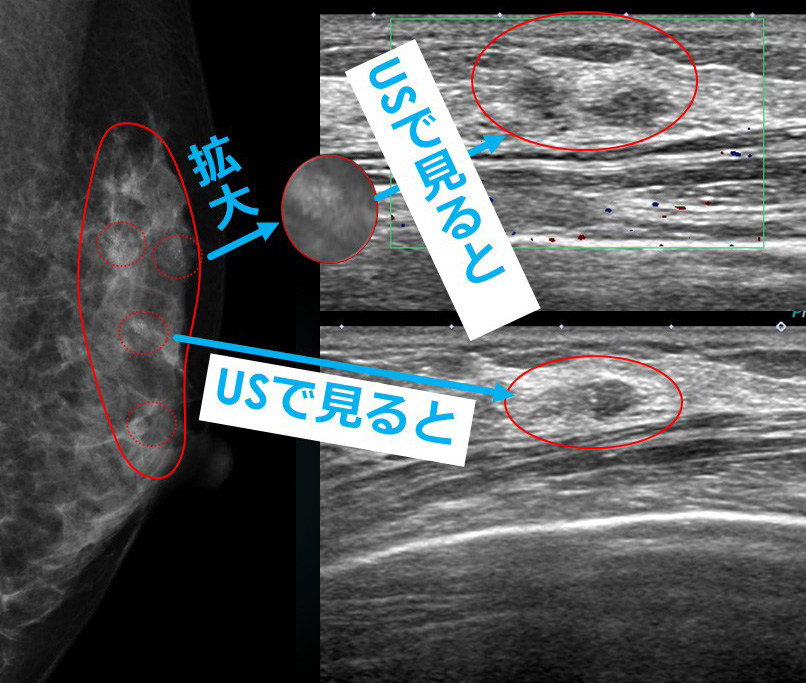

集簇した石灰化が区域性に並びカテゴリーⅤ(Ⅳ)

エコーでは、(石灰化に相当する部位に一致して)複数の「石灰化を含むlow echo」が認識できます。

★エコーで確認できるので(ST-MMTするまでもなく)、初診日にそのままMMTE施行しました。

どうやら、前医の技師さんは(前医からの診療情報提供には、技師によるエコーレポートがついていたので技師がエコーをしたことが判明してます)申し訳ないけど「誤った認識(正常乳腺のキラキラなどを捉えた)」だったようです。

今回に関しては、その(前医での技師によるエコーレポートが指摘している)所見の位置が正しくないと、私自身がエコーして確認しているからなんだ。

私自身がエコーして「これが病変の所見だ」と判断した部位より、「かなり」乳頭に近い部位を所見としているし、実際それに従ってCNB(前医ではCELEROでもMMTEでもなくCNBしている)している部位が「針跡」から解るんだけど、全く不適切(乳頭近辺)なので、そう判断したんだ。

実際の病変の位置は乳頭より「かなり上」なんだけど、その所見が読み切れなかったんだろうね。